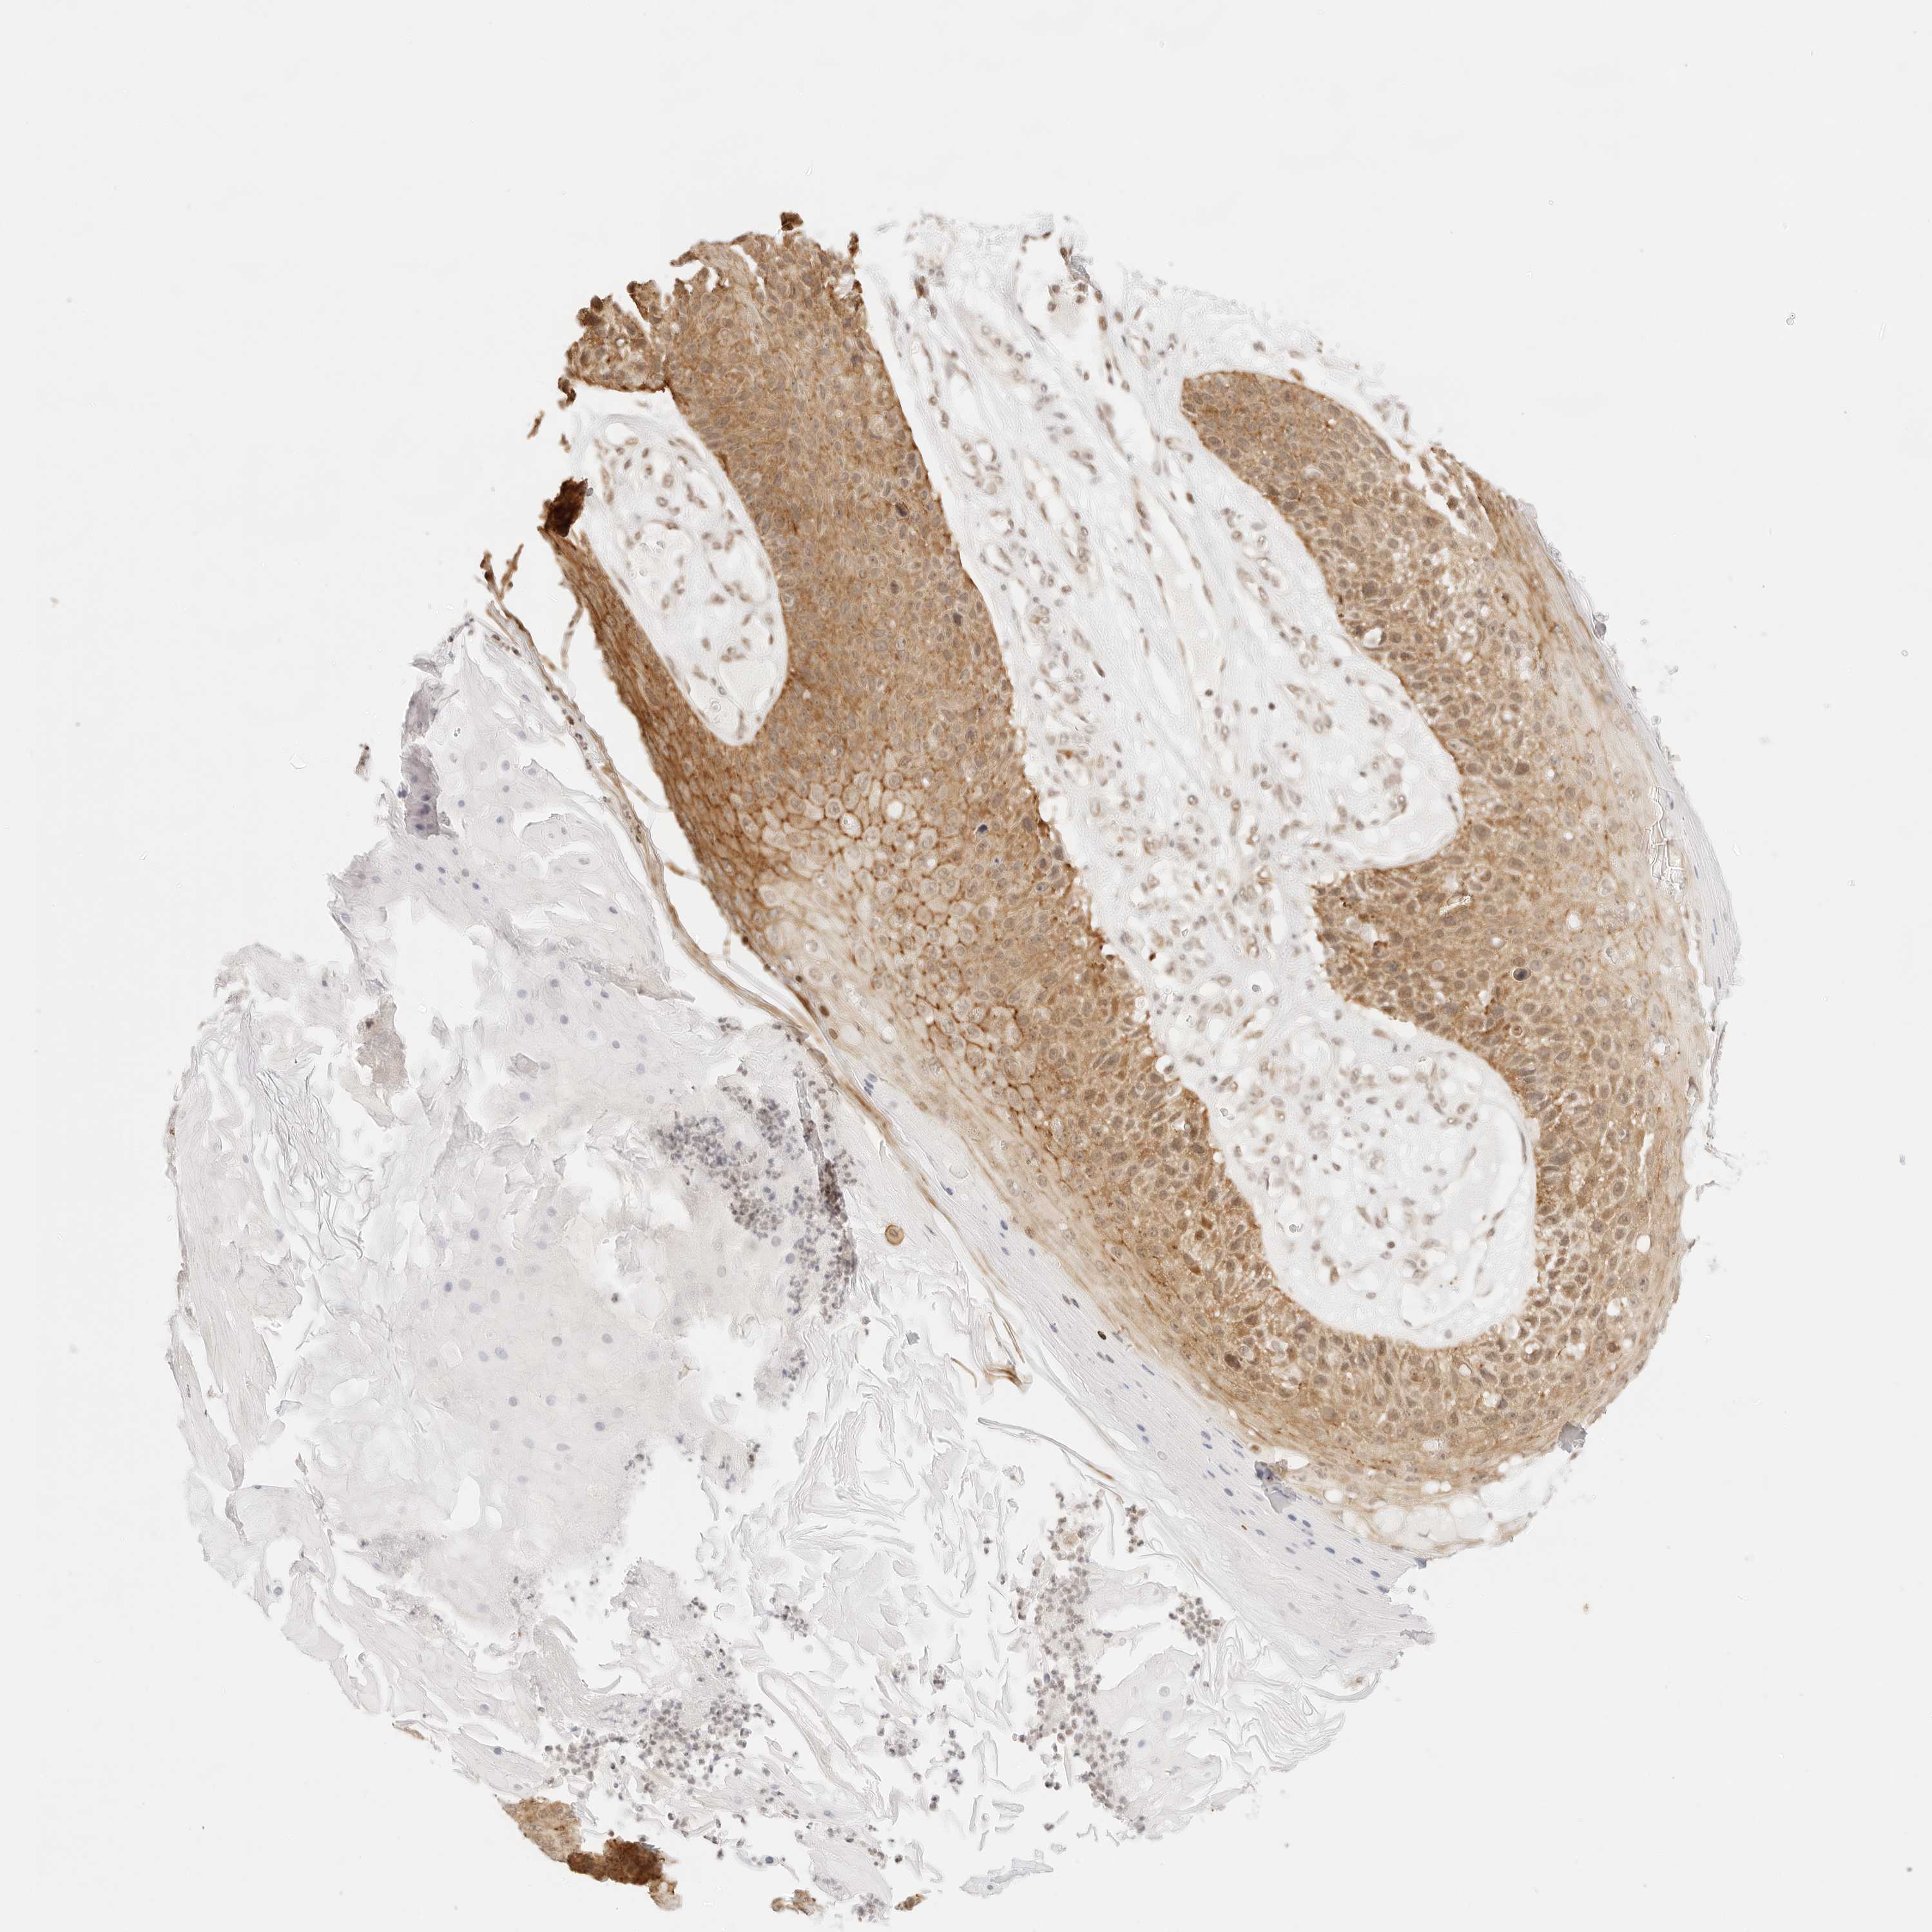

SKIN CANCER - Protein expressioni

A mouse-over function shows sample information and annotation data. Click on an image to view it in a full screen mode. Samples can be filtered based on level of antibody staining by selecting one or several of the following categories: high, medium, low and not detected. The assay and annotation is described here.

Each image is clickable and will lead to virtual microscopy that enables deeper exploration of all samples and also displays staining intensity scores, fraction scores and subcellular localization as well as patient and tissue information for each sample.

Antibody CAB010337

Squamous cell carcinoma, NOS